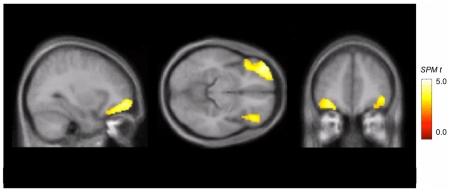

METHODOLOGY/PRINCIPAL FINDINGS: In the present study, positron emission tomography with the tracer alpha-[(11)C]methyl-L-tryptophan ((11)C-AMT) was used to compare 5-HT synthesis capacity in two groups of adult males from a 21-year longitudinal study (mean age +/- SD: 27.1+/-0.7): individuals with a history of childhood-limited high physical aggression (C-LHPA; N = 8) and individuals with normal (low) patterns of physical aggression (LPA; N = 18). The C-LHPA males had significantly lower trapping of (11)C-AMT bilaterally in the orbitofrontal cortex and self-reported more impulsiveness. Despite this, in adulthood there were no group differences in plasma tryptophan levels, genotyping, aggression, emotional intelligence, working memory, computerized measures of impulsivity, psychosocial functioning/adjustment, and personal and family history of mood and substance abuse disorders.

方法/主要发现:在本研究中,使用正电子发射断层扫描与示踪剂 alpha-[(11)C]甲基-L-色氨酸 ((11)C-AMT) 比较了来自 21 年纵向研究的两组成年男性的 5-HT 合成能力(平均年龄 +/- SD:27.1+/-0.7):有儿童期有限高身体攻击史的个体(C-LHPA;N=8)和正常(低)身体攻击模式的个体(LPA;N=18)。C-LHPA 男性双侧眶额皮质对 (11)C-AMT 的捕获明显较低,并且自我报告的冲动性更高。尽管如此,在成年期,两组在血浆色氨酸水平、基因分型、攻击性、情绪智力、工作记忆、冲动性的计算机测量、心理社会功能/适应、个人和家庭的情绪和物质滥用障碍史方面没有差异。